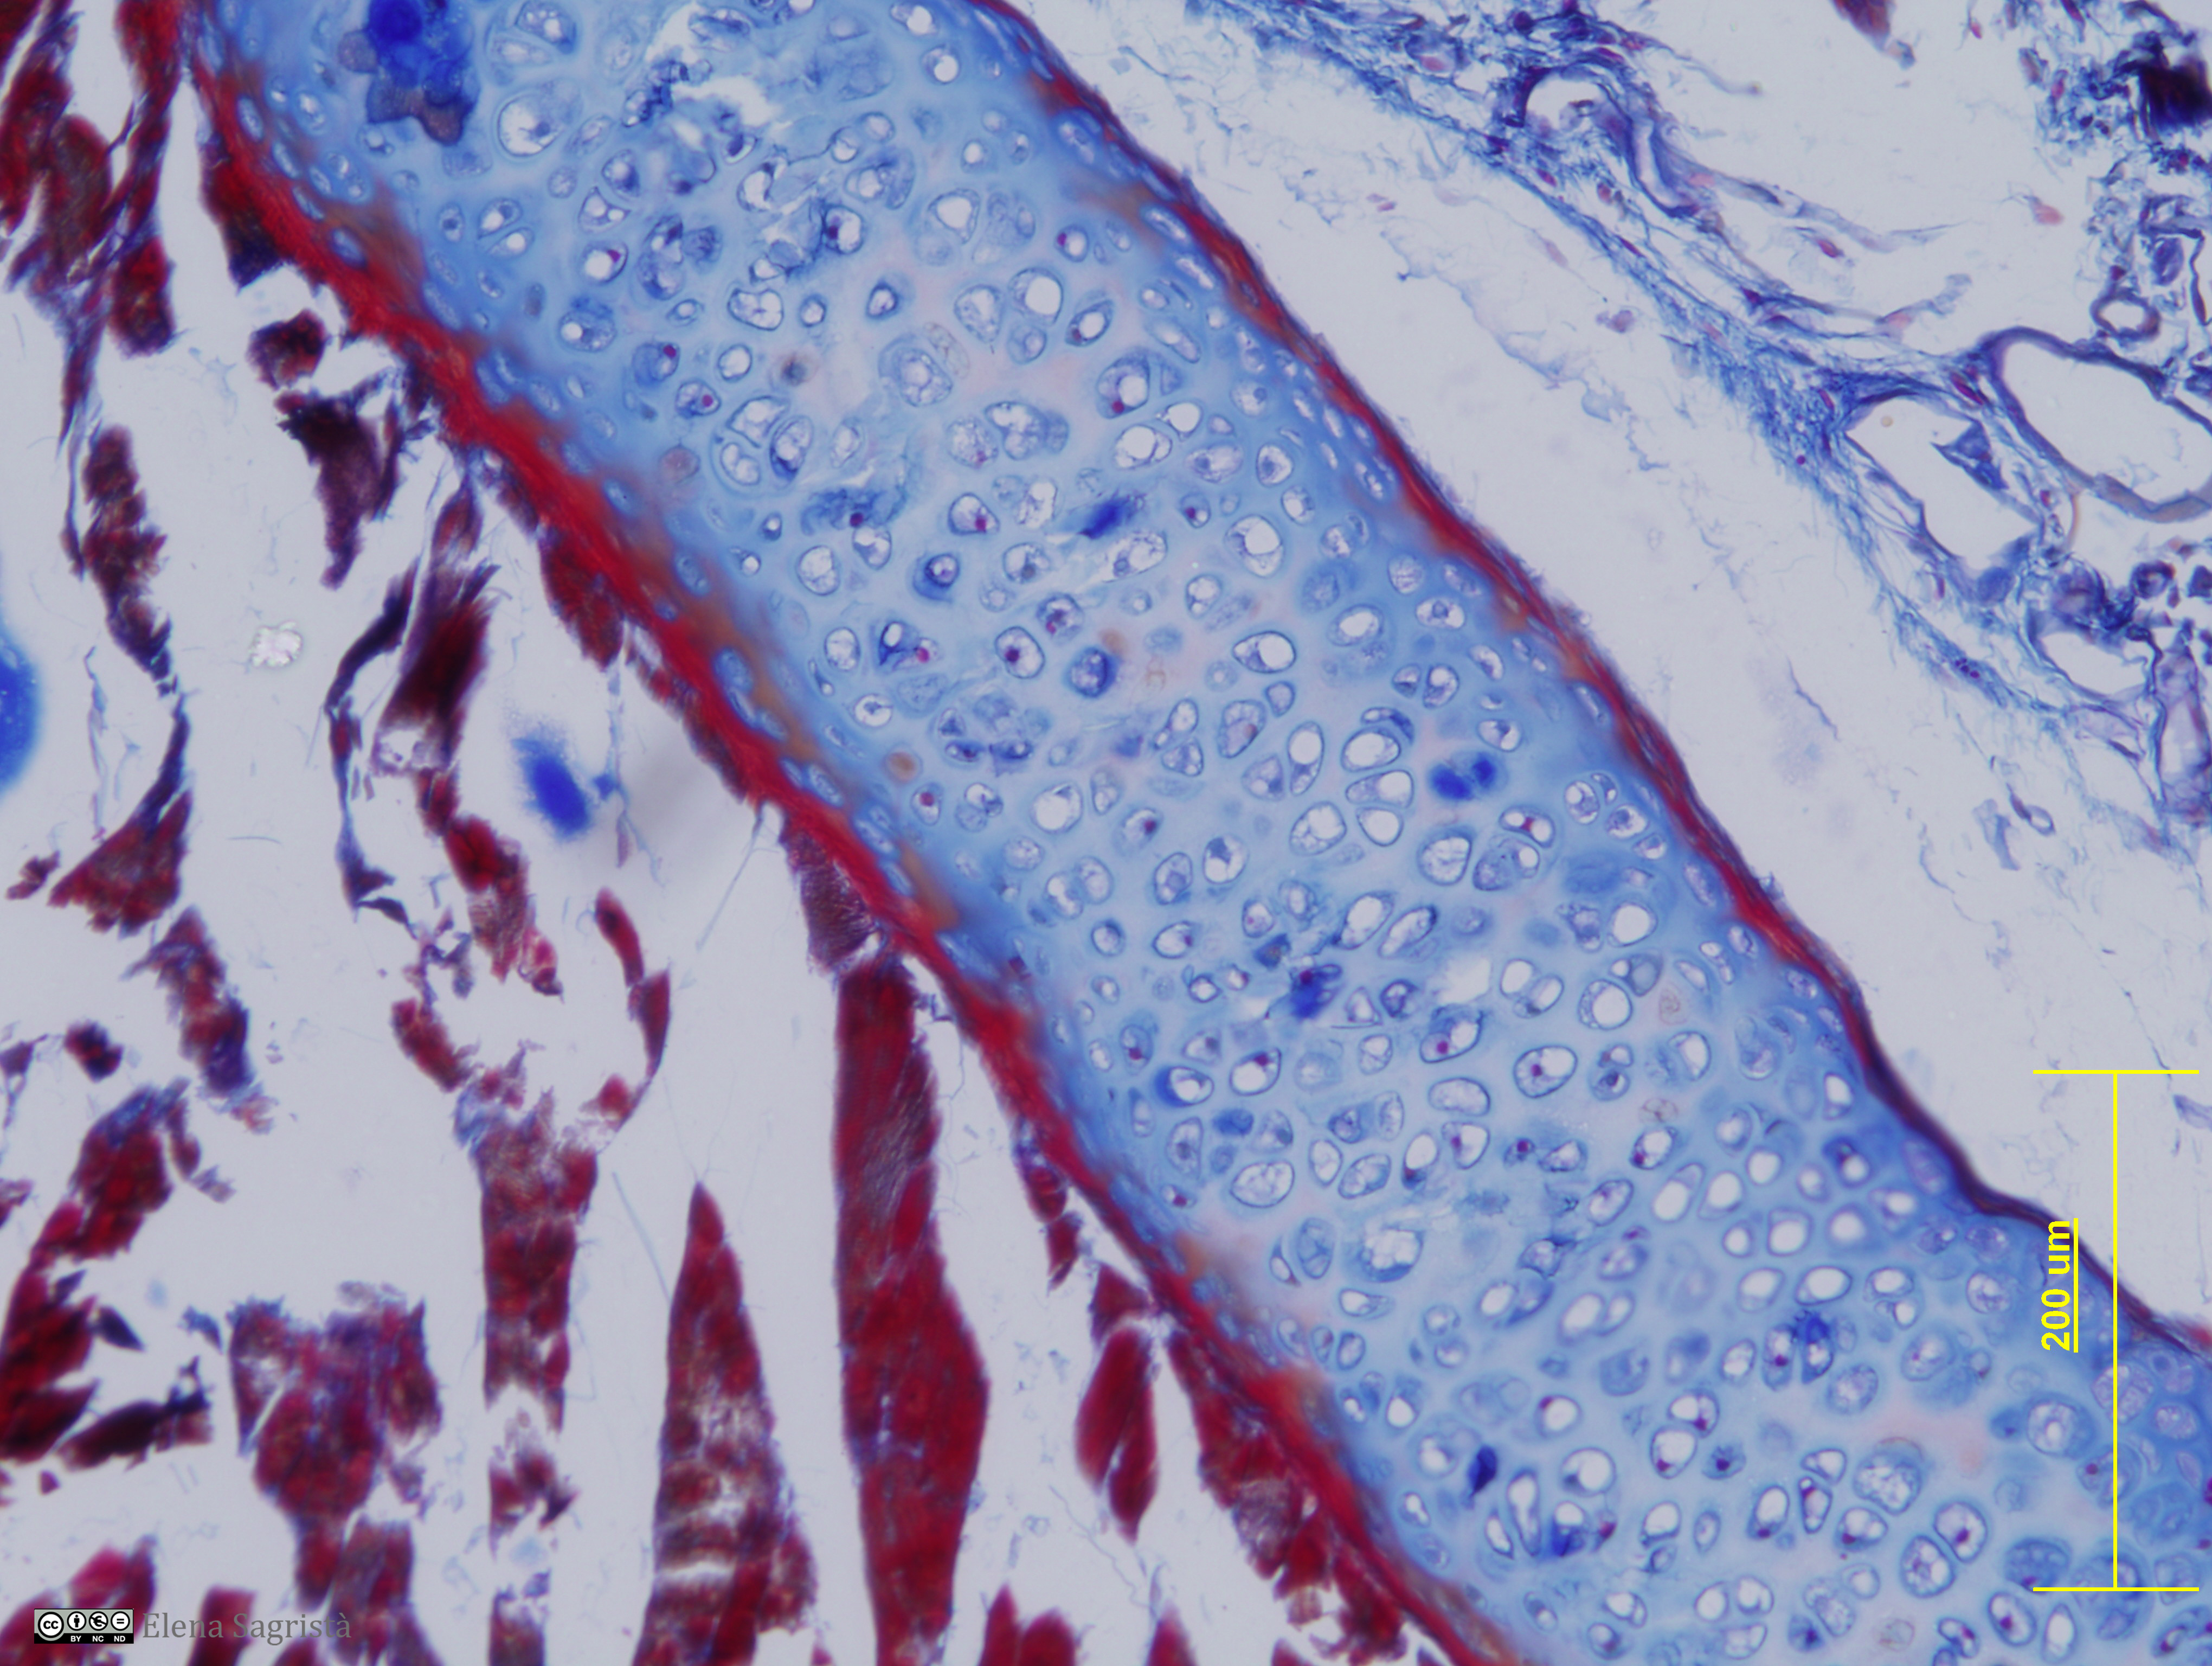

Histologia imatges: 04 Teixit cartilaginós

Imatges de preparacions histològiques de Teixit cartilaginós. Microscopia òptica.